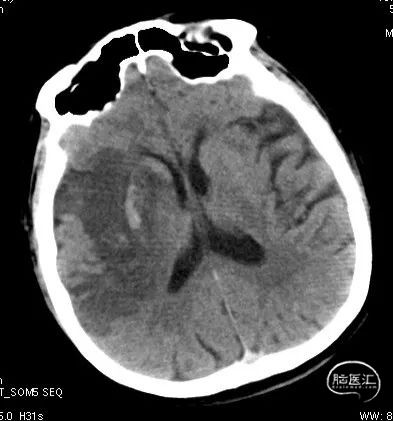

急诊颅脑CT+CTA:多发腔梗,ASPECTS评分:8分;CTA示右侧M1闭塞。

急诊颅脑CT+CTA